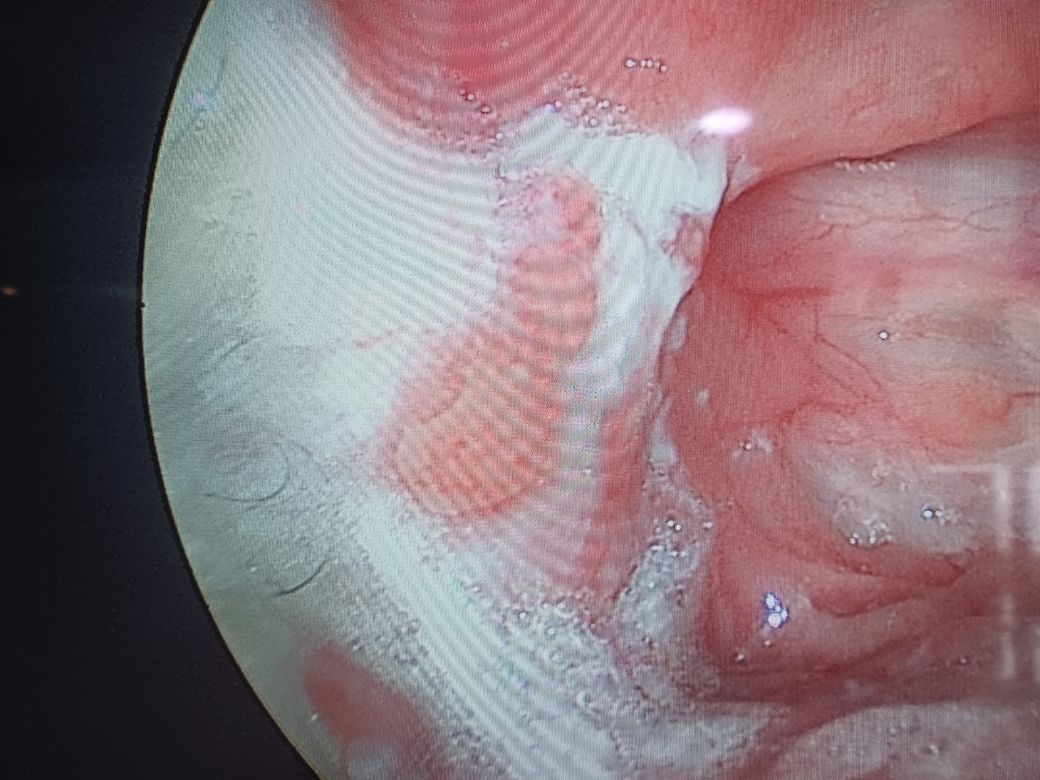

몇주전부터 목에 이물감이느껴지고 삼킬때 목에 뭐가 걸려있는거같아요 병원에서는 흰색가운데 부분이 이상하다고 하던데 사진한번봐주실수 있을까요

• 1번 째 사진